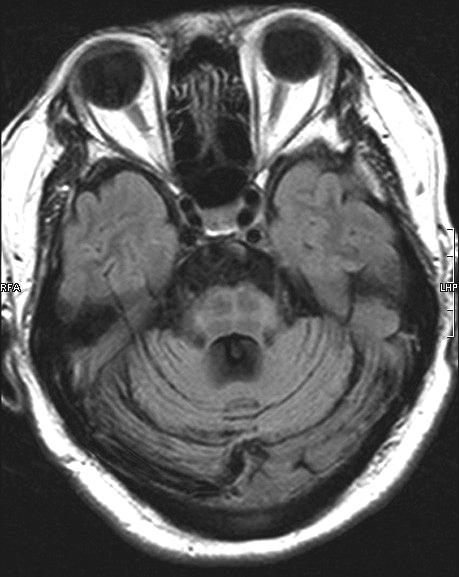

ผู้ป่วย MSA สามารถมีอาการร่วมอื่นๆ นอกเหนือจากอาการทางระบบประสาทอัตโนมัติพาร์กินโซนิซึม และอาการของสมองส่วนหลัง. อาการทาง pyramidal signs ดังเช่น brisk tendonreflexes, spasticity, extensor plantar responses และ pseudobulbar palsy มักพบได้บ่อย และสามารถตรวจพบได้ในช่วงแรกของผู้ป่วย MSA. อาการ dementia ถึงแม้ว่าจะพบน้อย และไม่เด่นชัด ถ้าเกิดขึ้นจะเป็นลักษณะอาการของ frontal lobe โดยส่วนใหญ่การวินิจฉัยโรค MSA จะอาศัยลักษณะอาการดังที่กล่าวไว้ข้างต้น ร่วมกับ diagnostic criteria ที่ได้กำหนดขึ้น.13 การตรวจทางห้องปฏิบัติการ โดยเฉพาะการตรวจ MRI จะช่วยบ่งบอกถึงรอยโรค และสนับสนุนลักษณะอาการที่เด่นในผู้ป่วยรายนั้นว่ามีพยาธิสภาพชัดเจนในสมองส่วนใด ดังเช่น MRI ในผู้ป่วย MSA-C มักปรากฏลักษณะของ brainstem and cerebellar atrophy. ลักษณะผิดปกติทาง MRI ที่พบได้มากกว่าร้อยละ 50 ของผู้ป่วย MSA โดยทั่วไป โดยเฉพาะในกลุ่ม MSA-P คือ hypointense signals on T2-weighted images เนื่องจากการสะสมของธาตุเหล็ก ร่วมกับ slit-like hyperintense signals on T2-weightd images ในส่วนของ putamen ส่วนนอก ลักษณะความผิดปกติของสมองส่วน Pons ซึ่งเกิดเนื่องจากการเสื่อมของ transversed pontine fibers และ midline raphe โดยที่ tegmentum ปกติ ทำให้ภาพของ MRI ในสมองส่วนนั้นมีลักษณะคล้าย Hot-cross bun (ภาพที่ 8)

ภาพที่ 8. Hot-cross bun sign.